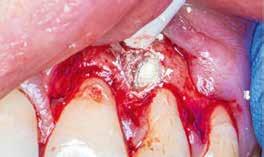

4. a–b. ábra: A reszorbciós üreg Biodentine-nel való feltöltése. Intraoperatív (a) és radiológiai felvétel (b). – 5. ábra: Az öt hónappal később látható állapot. Nem észlelhetők gyulladás fennállására utaló jelek.

gyökércsatornában lévő pulpát is részlegesen eltávolítottuk. A sebészi feltáráshoz szükséges metszést a frenulum mellől indítottuk, majd intrasulcularisan, papillakímélő módon a szemfogig vezettük. A lebeny felemelését követően a csontos falú üregből a granulációs szövetet egy éles exkavátor segítségével eltávolítottuk.

A gyökértömés elkészítése során meleg vertikális kompakciós technikát alkalmaztunk, sealerként pedig CeraSeal-t (Meta Biomed; 3. ábra) használtunk. A reszorbciós üreget Biodentine-nel (Septodont; 4. a–b ábra) töltöttük fel. A reszorbcióval érintett területtől koronális irányba elhelyezkedő csatornaszakaszt pedig tisztán meleg guttaperchával kezeltük. Ezt követően a lebenyszéleket visszafektettük, és varratok behelyezésével eredeti pozíciójuknak megfelelően rögzítettük. A koronai részt kompozit tömőanyag segítségével állítottuk helyre. Kontrollvizsgálatra 5, illetve 30 hónappal később került sor (5. ábra). A csontos telődés jelei már 5 hónap után észlelhetők voltak (6. a–c ábra). A 30 hónappal később végzett kontroll során sem találtunk csontban lévő lézióra, törésre vagy egyéb pathológiás elváltozásra utaló jeleket (7. a–b ábra)